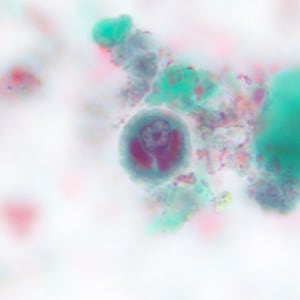

A 37-year-old man began experiencing severe diarrhea about one week after attending a family social event. At the request of his medical provider, a fecal specimen collected in the two-vial system consisting of one vial with 10% formalin and one vial with Zn-PVA (zinc-based polyvinyl alcohol) was submitted for examination.